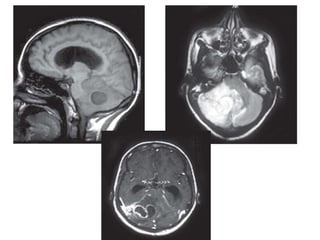

Sagittal T1W (A) and T2WI axial (B) MR images showing a

cystic lesion with signal intensity similar to CSF in the fourth

ventricle with resultant obstructive hydrocephalus —

intraventricular cysticercus